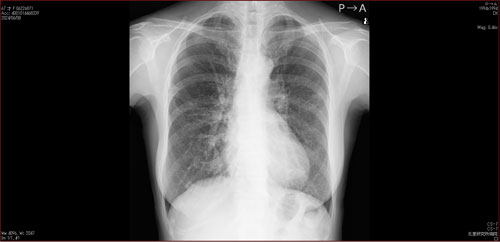

肺X線画像

- 2023.08.03 肺炎後の要観察(1)(国立系病院)